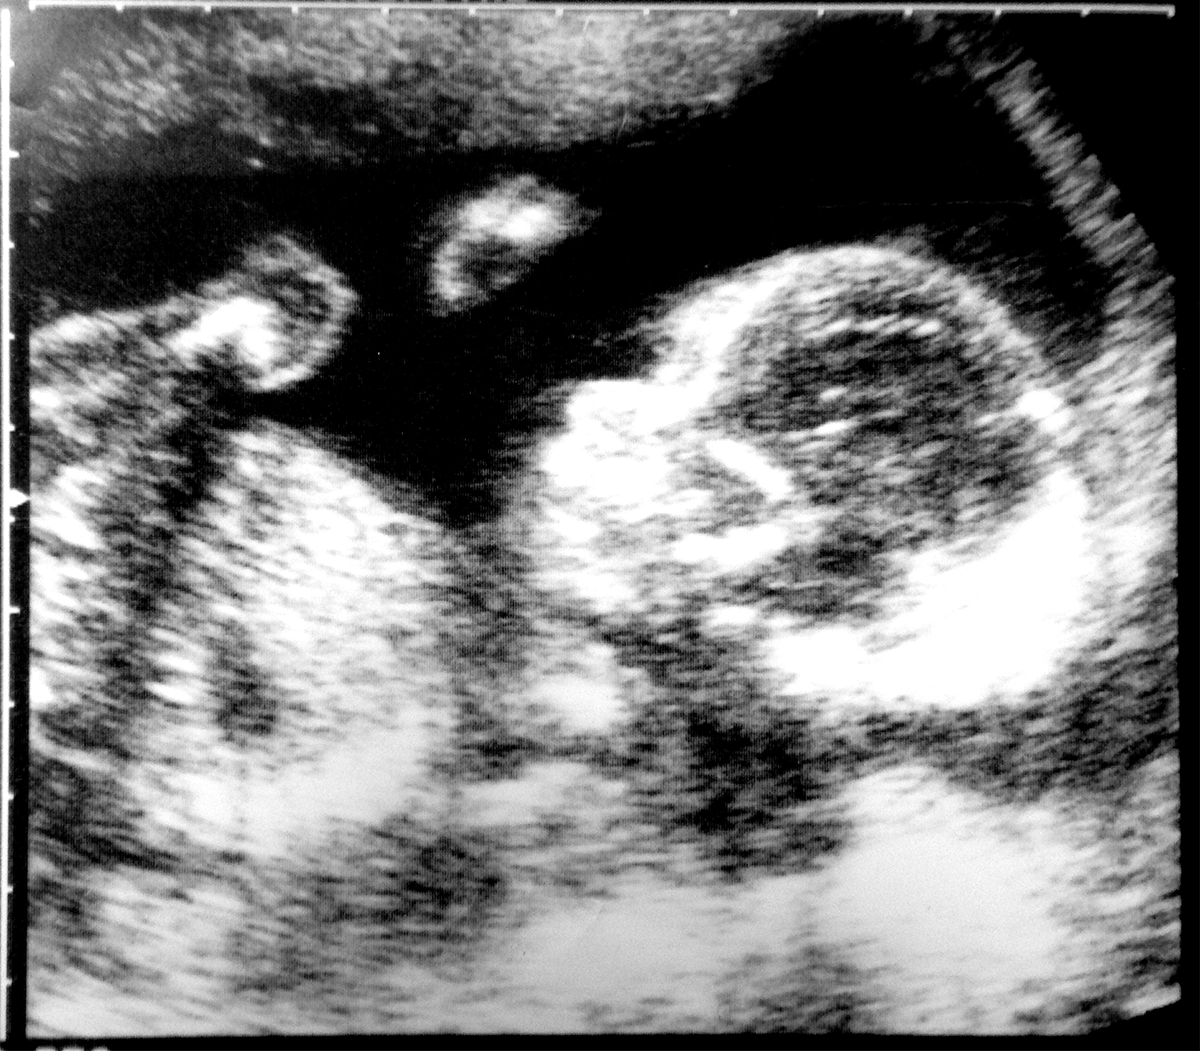

The foetal phase starts at the end of week 8. During this time, the body's organs and tissues continue to grow and will start to work. The foetus will grow in length through the second trimester to 24 weeks gestation.

By 24 weeks gestation, the foetus will have developed sufficiently that it is possible for the baby to be born and to be viable or live outside the mother's uterus. This is only possible because the last body system to develop functionality, the respiratory system, starts to develop its functionality around weeks 21-23. Currently the earliest known live birth of a baby who survives into childhood is a baby born around 22 week's gestation.